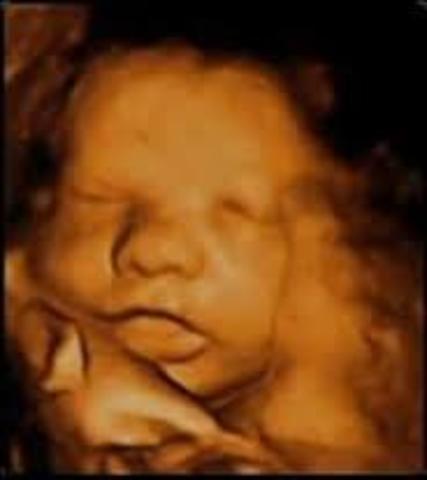

La semana 19 es muy importante en el embarazo ya que tanto tu cuerpo como el del bebé sufren nuevos cambios. Es posible que tu médico te pida una segunda ecografía, donde podrás ver a tu bebé cómo ha crecido estas semanas y descartar si hay algún tipo de complicación.

Estás en la semana veinte de embarazo y es posible que te realices la segunda ecografía, para comprobar que tu bebé está bien formado. Examinarán su cuerpo y podrán ver si hay alguna anomalía. Si aún no has sentido a tu bebé a partir de esta semana ya puede ser que sientas las famosas pataditas en tu barriga.

En la semana 32 de embarazo tu bebé y todo su organismo ya están preparándose para lo que será la vida fuera de la placenta que los ha albergado todos estos meses. Medirá unos 47 centímetros y puede que llegue a pesar unos dos kilos.

Los riñones de tu bebé producen orina y sus pulmones comienzan a respirar, su cerebro continúa creciendo y las uñas ya llegan a la punta de sus dedos, por lo que deberás cortárselas al poco tiempo de nacer. Su rostro también es más expresivo y a veces sacará la leng